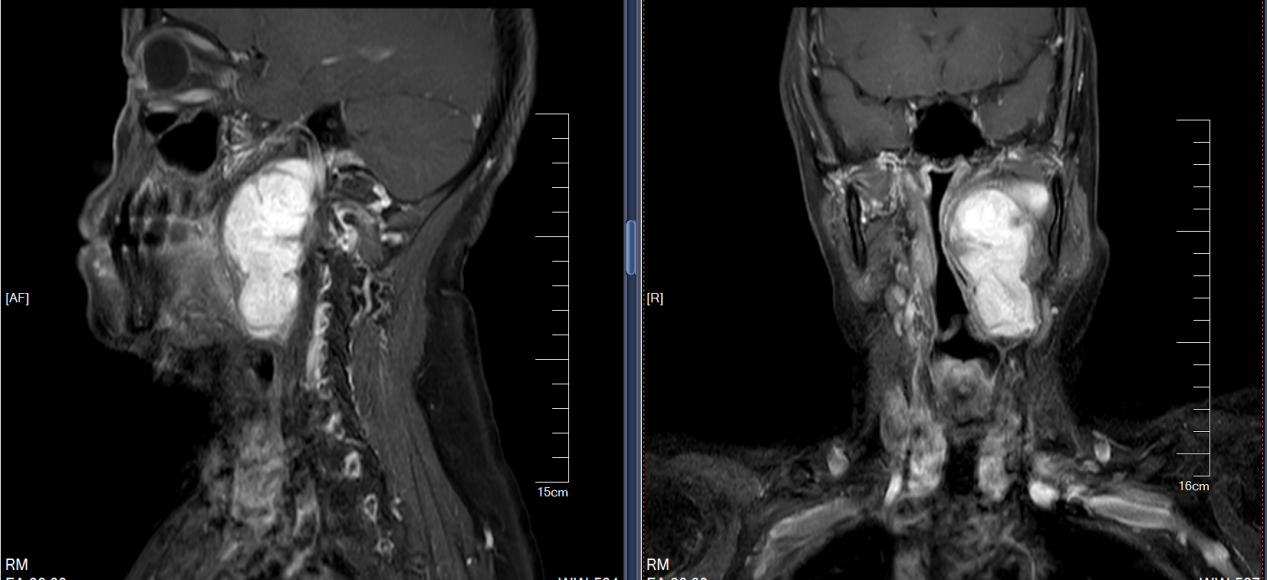

面对这一复杂病例,我院头颈外科高度重视,组织了包括影像科、麻醉科在内的多学科专家进行联合会诊。通过精细的术前影像学评估,团队全面掌握了肿瘤与颈内动脉、颅神经等重要结构的关系,并预判了手术中可能出现的各种风险,最终制定了详尽周密的手术方案和应急预案。

在充分的术前准备基础上,由郭海鹏主任医师带队,手术团队凭借丰富的经验和精湛的技术,选择了最佳的手术入路,在清晰暴露术野的同时,小心翼翼地分离、保护周边重要的血管和神经。术中,团队操作精准、轻柔,最终将肿瘤完整切除,未损伤重要神经血管,最大程度地保留了患者的功能。手术过程顺利,患者生命体征平稳。

图片 2.png图片 3.png